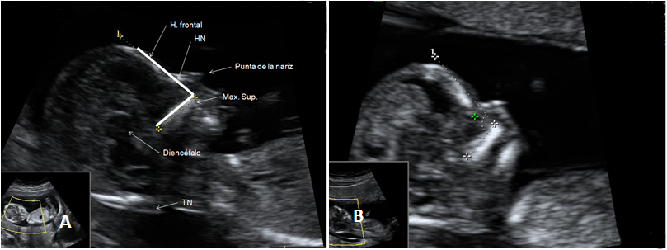

La ausencia de hueso nasal y tener un pliegue nucal aumentado son marcadores que se detectan en la ecografía de la semana 12 y que pueden significar que el feto padece alguna alteración cromosómica, como es el síndrome de Down.

Ecografía de hueso nasal ausente

En A se aprecia el hueso nasal (flecha) en una gestación normal de 12 semanas. En B, un embrión de 12 semanas con síndrome de Down, en el que el hueso nasal está ausente y además tiene una translucencia nucal aumentada.

Imagen del hueso nasal ausente (A) y pliegue nucal aumentado (B)